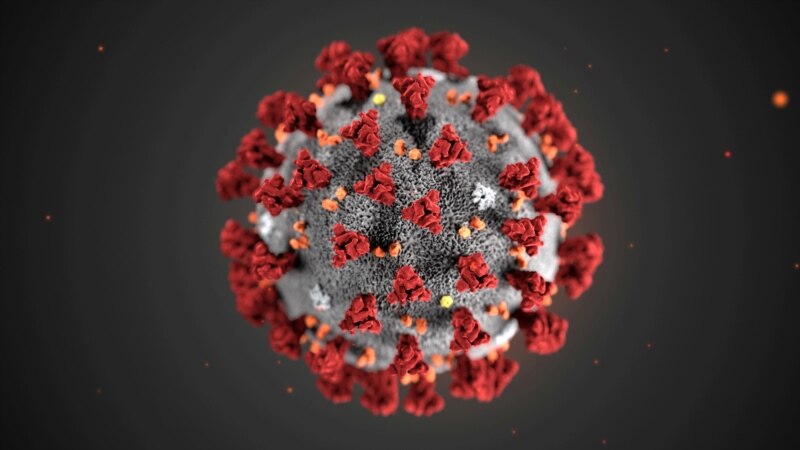

Health Experts Prepared to Deal with Coronavirus Epidemic

Efforts Intensify to Contain New Coronavirus

New Coronavirus: What We Know